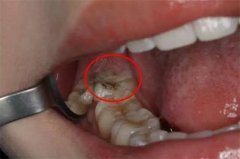

近日,河北唐山一女子拔智齿,因为智齿长得特别牢固,牙医拿着钳子生拉硬拽使劲摇晃了一小时才将两颗智齿拔下来,旁人看到这夸张的过程被逗笑。

2、形成蛀牙

如果智齿已经变成了蛀牙的情况,而且没有办法补牙,那么就需要进行拔除,以绝后患。